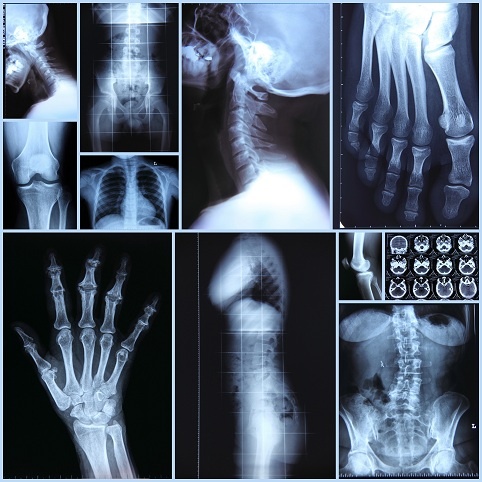

Современное оборудование для рентгеновской диагностики: безопасность и эффективность

Рентген – это один из наиболее распространенных методов диагностики в медицине. Он основан на использовании рентгеновских лучей для создания изображения внутренних органов и тканей человека. Сегодня рентгеновская технология значительно продвинулась, и современное оборудование для рентгена стало намного более безопасным, чем его предшественники. Одним из главных достоинств современного оборудования для рентгена является его способность минимизировать дозы радиации, которые получает пациент. Новые технологии, такие как цифровая рентгенография, позволяют получать изображения высокого качества при использовании значительно меньших доз радиации, чем было раньше. Более того, современное оборудование для рентгена имеет встроенные механизмы контроля дозы радиации, которые позволяют точно регулировать количество излучения, которое получает пациент. В дополнение к этому, современное оборудование для рентгена имеет множество других функций, которые делают его намного более безопасным и эффективны

Рентген – это один из наиболее распространенных методов диагностики в медицине. Он основан на использовании рентгеновских лучей для создания изображения внутренних органов и тканей человека. Сегодня рентгеновская технология значительно продвинулась, и современное оборудование для рентгена стало намного более безопасным, чем его предшественники.

Одним из главных достоинств современного оборудования для рентгена является его способность минимизировать дозы радиации, которые получает пациент. Новые технологии, такие как цифровая рентгенография, позволяют получать изображения высокого качества при использовании значительно меньших доз радиации, чем было раньше. Более того, современное оборудование для рентгена имеет встроенные механизмы контроля дозы радиации, которые позволяют точно регулировать количество излучения, которое получает пациент.

В дополнение к этому, современное оборудование для рентгена имеет множество других функций, которые делают его намного более безопасным и эффективным, чем его предшественники. Например, оно может автоматически корректировать изображение в реальном времени, чтобы уменьшить дозу радиации, которую получает пациент. Кроме того, современные рентгеновские аппараты могут быть снабжены специальными экранами и фильтрами, которые уменьшают количество рентгеновских лучей, проходящих через пациента.